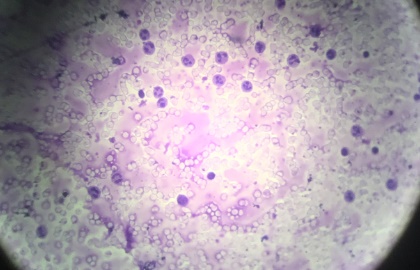

Los alumnos y alumnas de 3ºESO realizaron una actividad de lo más interesante, que consistió en la obtención de sangre en fresco mediante punción capilar y observación en microscopio óptico de los elementos que componen la sangre: eritrocitos y leucocitos.